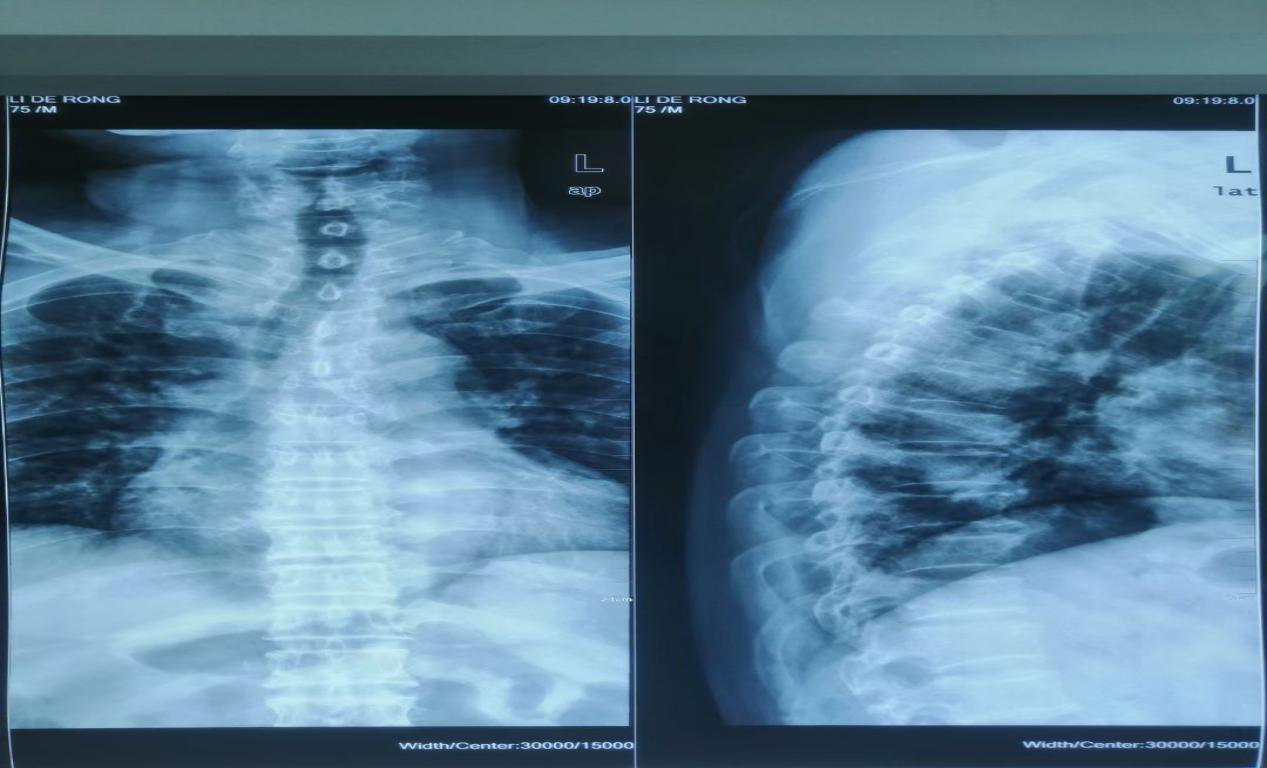

近日,一位76老年患者来我院就诊,患者过年骑电动车走亲戚不慎摔伤,高位胸椎5椎体压缩性骨折,乌海市人民医院骨科主治医师刘涛详细了解患者病情后予以手术治疗。术前,刘涛及脊柱外科组对患者手术部位进行了精准定位,既要保证手术高成效。有要避免伤及周边神经。术中,刘涛采用微创技术“胸椎骨折球囊扩张椎体成型术”,用球囊撑起患者碎裂脊椎,再用骨水泥进行填充。手术前后仅用时20分钟,手术中创伤小,出血少约5ml。手术效果立竿见影,术后患者胸背部受限感明显缓解,活动自如。翻身起坐疼痛感也大幅消失。